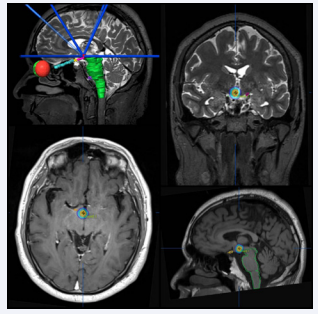

Radiosurgery

Stereotactic Radiosurgery (SRS) is an attractive approach that does not require an invasive approach. The mean goal of SRS for HH is to deliver doses high enough to affect epileptogenesis without exceeding the tolerance of surrounding structures. Nowadays, modern radiosurgical devices can deliver high dose radiation providing a chance to achieve seizure freedom without hypothalamic or cranial nerve damage. The first successful SRS treatment of HH with seizures was reported by Arita et al., in 1998 [60]. In 2000, the Marseille group reported a series of 8 patients, with 50% cases attaining Engel Class I by Gamma Knife Surgery (GKS), for the 2006, the data were updated, including more than 60 patients who had undergone GKS, with similar improvement results [55]. The meticulous treatment planning and very tight dose distribution are essential to delivering doses without injuring the nearby critical structures. The mean size of HH in the largest series of SRS was 19 mm in diameter, but SRS can be realized in lesions smaller than 30 mm by using steep dose gradients around the target [60], while the size for ideal SRS candidate was reported less than 16 mm [61]. Régis et al., found a clear correlation between dose and efficacy; the marginal dose was >17 Gy in all patients in whom seizure freedom was achieved and all patients who received <13 Gy showed incomplete seizure control [60]. These studies demonstrate that SRS is an effective treatment for selected patients. Some reports indicated that SRS is as effective as microsurgical resection and safer [55,62]. However, it is important to remember that, like HH microsurgical resection complications, SRS can result also in permanent neurological sequelae [63,64]. Ablashowed that GKS was associated with few complications and about 60% seizure- free rate as part of a multimodal treatment protocol [65]. No serious complication has been reported with SRS but temporary worsening of seizures can be seen as early as 2 months after the procedure. Nevertheless, one of the main disadvantages with SRS is that clinical response can be slow (4-6 moths), and the patient remains exposed to the risks of persistent seizures for up to two years after the radiosurgical procedure, early results suggest variable outcomes. Régis et al., reported excellent early seizure response [55]. However, results in terms of long-term seizure freedom are not clear, but, the immediate effect on subclinical discharges turns out to play a major role in the dramatic improvement of sleep quality, behavior, and developmental learning acceleration at school (Figure 4).

Treatment planning MRI showing right type I HH outlined in sagittal,  axial and coronal views. The marginal dose (17 Gy) is displayed in yellow.

Figure 4: Treatment planning MRI showing right type I HH outlined in sagittal, axial and coronal views. The marginal dose (17 Gy) is displayed in yellow.